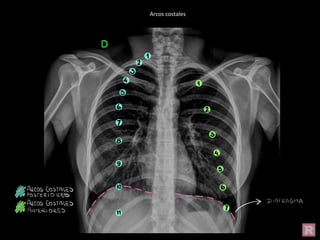

Arcos costales